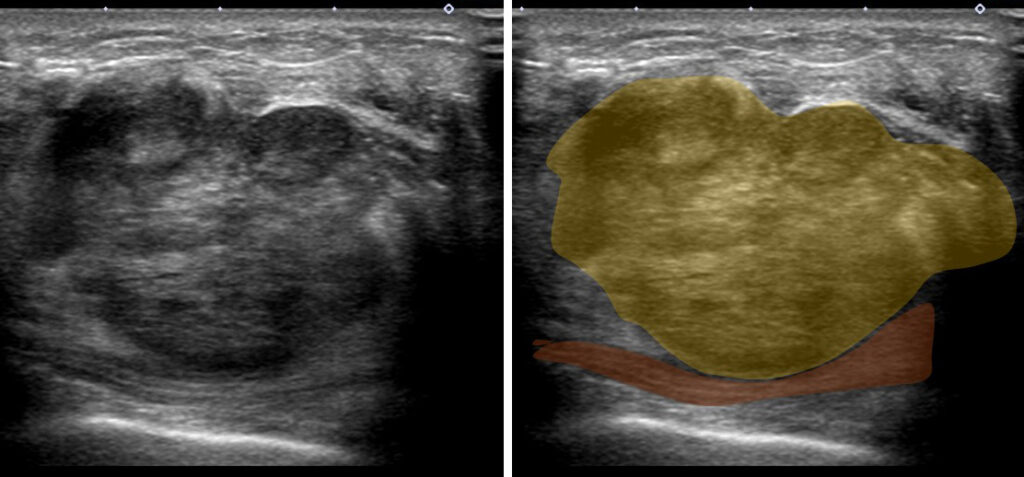

エコーで見ると…

裏側の筋層(大胸筋)とは接してはいるけど、浸潤しているのか?は不明

但し、

「接しているだけ?」にしろ、実際に「浸潤している?」にしろ

剥がしてしまっては、大胸筋側に「癌細胞を残存=胸壁再発」のリスクを抱えることとなる。

このようにする(した)のです。

このように、腫瘍から遠い部位は大胸筋から剥がしていって、腫瘍から近づいた地点から大胸筋も一緒に切除していくのです。

大胸筋は全切除する必要は無論なく、腫瘍の真裏(腫瘍床といいます)及びその周辺部分のみ合併切除するのです。

摘出した後にひっくり返すと、腫瘍床には大胸筋が一緒に切除されている様子が解りますね。